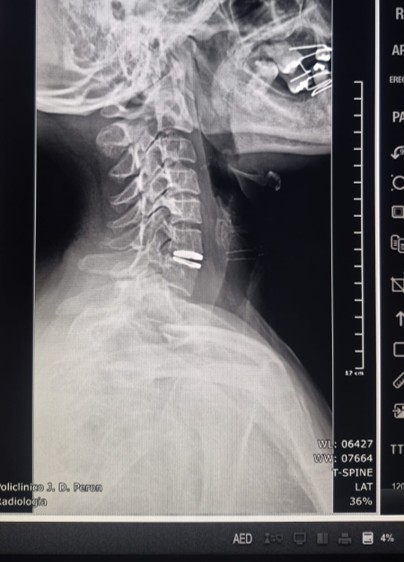

Por primera vez en Villa Mercedes, profesionales del sistema público de salud realizaron un reemplazo de disco cervical con prótesis discal móvil, una cirugía de alta complejidad que preserva la movilidad cervical y evita procedimientos más invasivos. La intervención se concretó el lunes dentro de los nuevos quirófanos del policlínico ‘Juan Domingo Perón’ y constituye un hecho inédito para el sistema sanitario local.

La paciente, una mujer de 48 años oriunda de Fraga, presentaba dolor cervical con irradiación a hombros, con impacto funcional. El procedimiento estuvo a cargo de Sebastián Heredia, médico neurocirujano, junto con el equipo de instrumentación quirúrgica integrado por Virginia Mora e Ivana Altamirano.